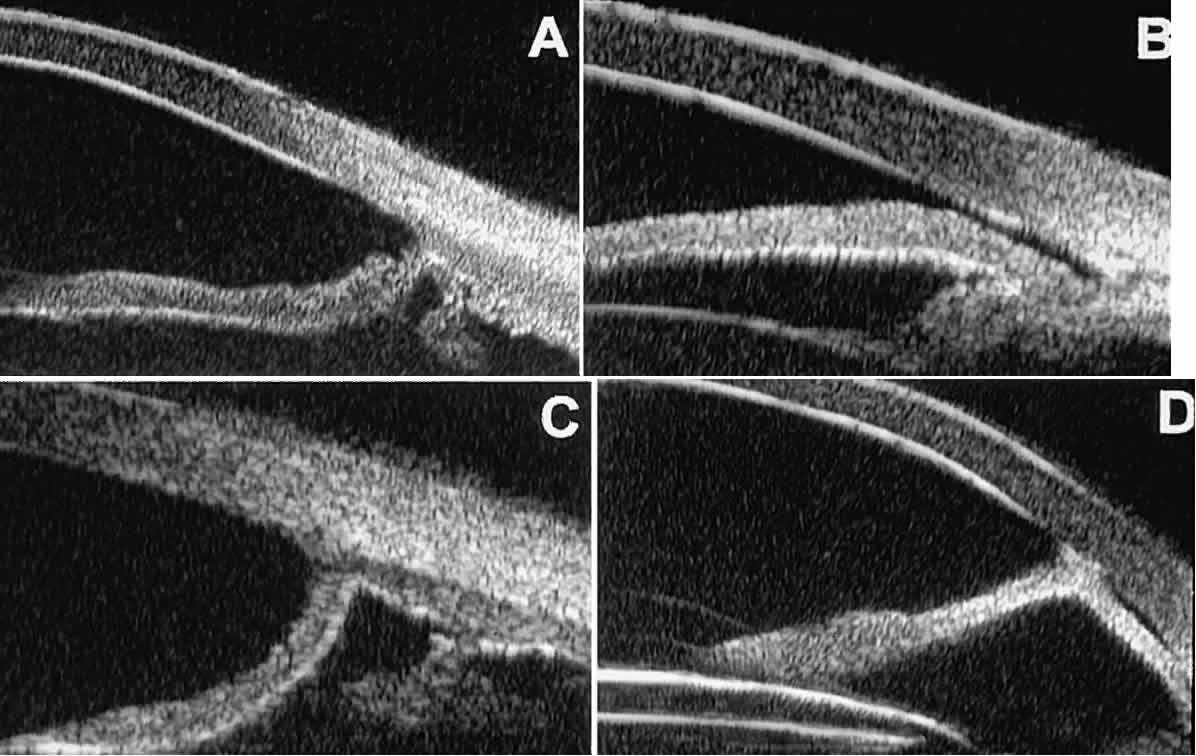

In eyes with a narrow angle, UBM shows the extent of angle closure, reveals the depth of the anterior and posterior chambers, and identifies pathologic processes pushing the lens and iris forward (Fig. 11).2–4,8 UBM has been able to differentiate between primary angle closure (i.e., cases of angle closure without additional pathology responsible for the anterior lens-iris displacement [see Fig. 11A] and secondary angle closure due to processes such as lens swelling and dislocation (see Fig. 11B), massive hemorrhagic retinal detachment pushing the lens and iris anteriorly (see Fig. 11C), and multiple neuroepithelial cysts of the iridociliary sulcus (see Fig. 11D).

Fig. 11. Angle configuration in eyes with angle-closure glaucoma. A. Primary angle-closure glaucoma with anterior displacement of lens and iris. B. Angle closure secondary to swollen, cataractous lens (phakomorphic angle closure). C. Angle closure secondary to massive hemorrhagic retinal detachment; the subretinal blood is evident in the lower right corner of the photograph. D. Angle closure secondary to multiple peripheral iris cysts.